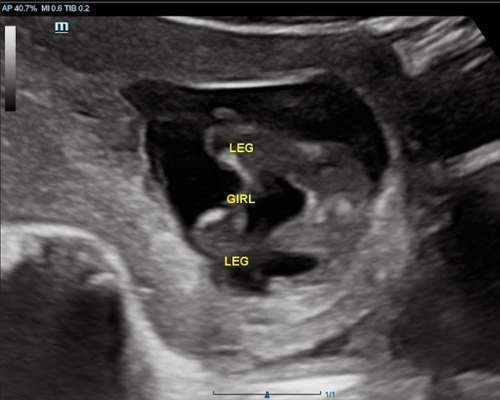

- 2D ultrasound to determine your baby’s gender

During the scan, the sonographer examines the baby’s genital area using ultrasound imaging to identify whether you are expecting a boy or a girl.